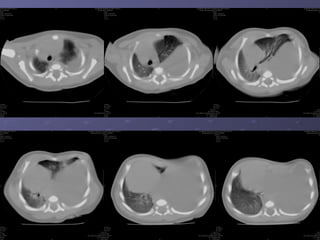

. Trước tiêm CQ

Chụp CT scannercó CQTMChụp CT scanner có CQTM . Trước tiêm CQ

- Chụp CT scannerChụp CT scanner (++90%): tiêm cản(++90%): tiêm cản

quang, đa dãy, dựng hình MPR, 3D mạchquang, đa dãy, dựng hình MPR, 3D mạch

máu.máu.

. Là khối choán chỗ đậm độ mô mềm,+_. Là khối choán chỗ đậm độ mô mềm,+_

đồng nhất, ++ cạnh sống trái, +_ dạng ‘tổđồng nhất, ++ cạnh sống trái, +_ dạng ‘tổ

ong’, nang khí or mức khí – dịch. Sau tiêmong’, nang khí or mức khí – dịch. Sau tiêm

cản quang, tăng tỉ trọng không đều, thấycản quang, tăng tỉ trọng không đều, thấy

rõ mạch máu nuôi.rõ mạch máu nuôi.

- Chụp CTscannerChụp CT scanner (++90%): tiêm cản(++90%): tiêm cản quang, đa dãy, dựng hình MPR, 3D mạchquang, đa dãy, dựng hình MPR, 3D mạch máu.máu. . Là khối choán chỗ đậm độ mô mềm,+_. Là khối choán chỗ đậm độ mô mềm,+_ đồng nhất, ++ cạnh sống trái, +_ dạng ‘tổđồng nhất, ++ cạnh sống trái, +_ dạng ‘tổ ong’, nang khí or mức khí – dịch. Sau tiêmong’, nang khí or mức khí – dịch. Sau tiêm cản quang, tăng tỉ trọng không đều, thấycản quang, tăng tỉ trọng không đều, thấy rõ mạch máu nuôi.rõ mạch máu nuôi.